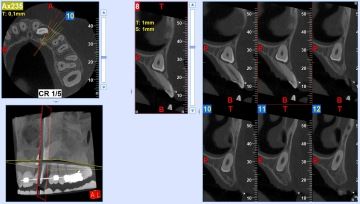

Před zákorkem většinou zhotovujeme 3D rentgenový snímek (CT) pro naplánování chirurgického přístupu . Po vytažení zubu vyplňujeme prostor kombinací kolagenu a APRF (plazma bohatá na růstové faktory). Velmi výrazně tím snižujeme riziko pooperačních komplikací.